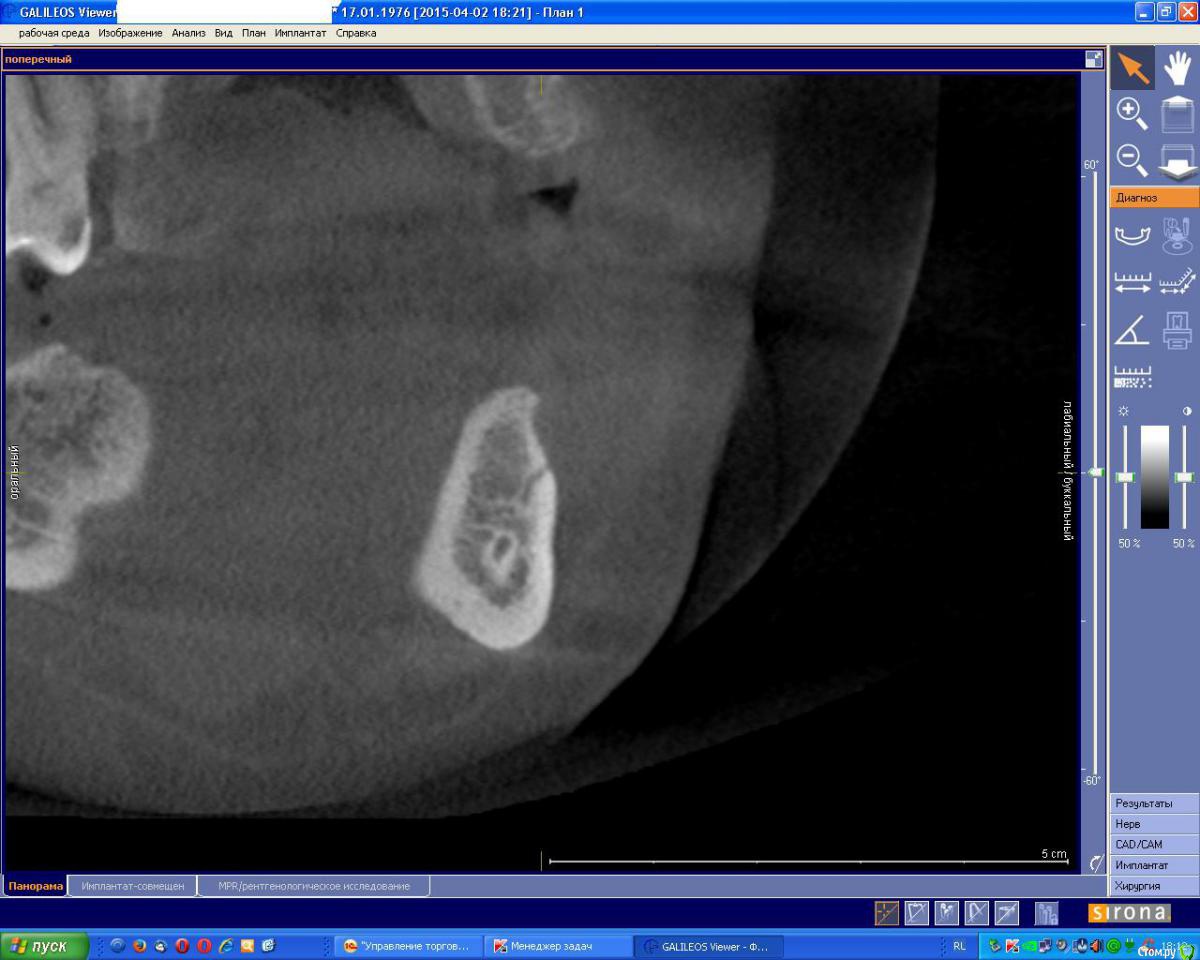

an_ver Опубликовано 4 мая, 2015 Поделиться Опубликовано 4 мая, 2015 На первом снимке мент.отверстие,на втором артерия? Доп.отверстие ментальное? Ссылка на комментарий

Alexey Doc Опубликовано 4 мая, 2015 Поделиться Опубликовано 4 мая, 2015 Думаю что да.нижнечелюстной канал иногда открывается не одним отверстием. Или Просто какая то нерегулярная артерия 1 Ссылка на комментарий

Kazankov.Egor Опубликовано 23 мая, 2015 Поделиться Опубликовано 23 мая, 2015 Предположу))) начнем считать зубки7-6(корень)-5(лунка)- канал подбородочного нерва?) Ссылка на комментарий

Kazankov.Egor Опубликовано 23 мая, 2015 Поделиться Опубликовано 23 мая, 2015 Мне кажется это в/ч) Ссылка на комментарий